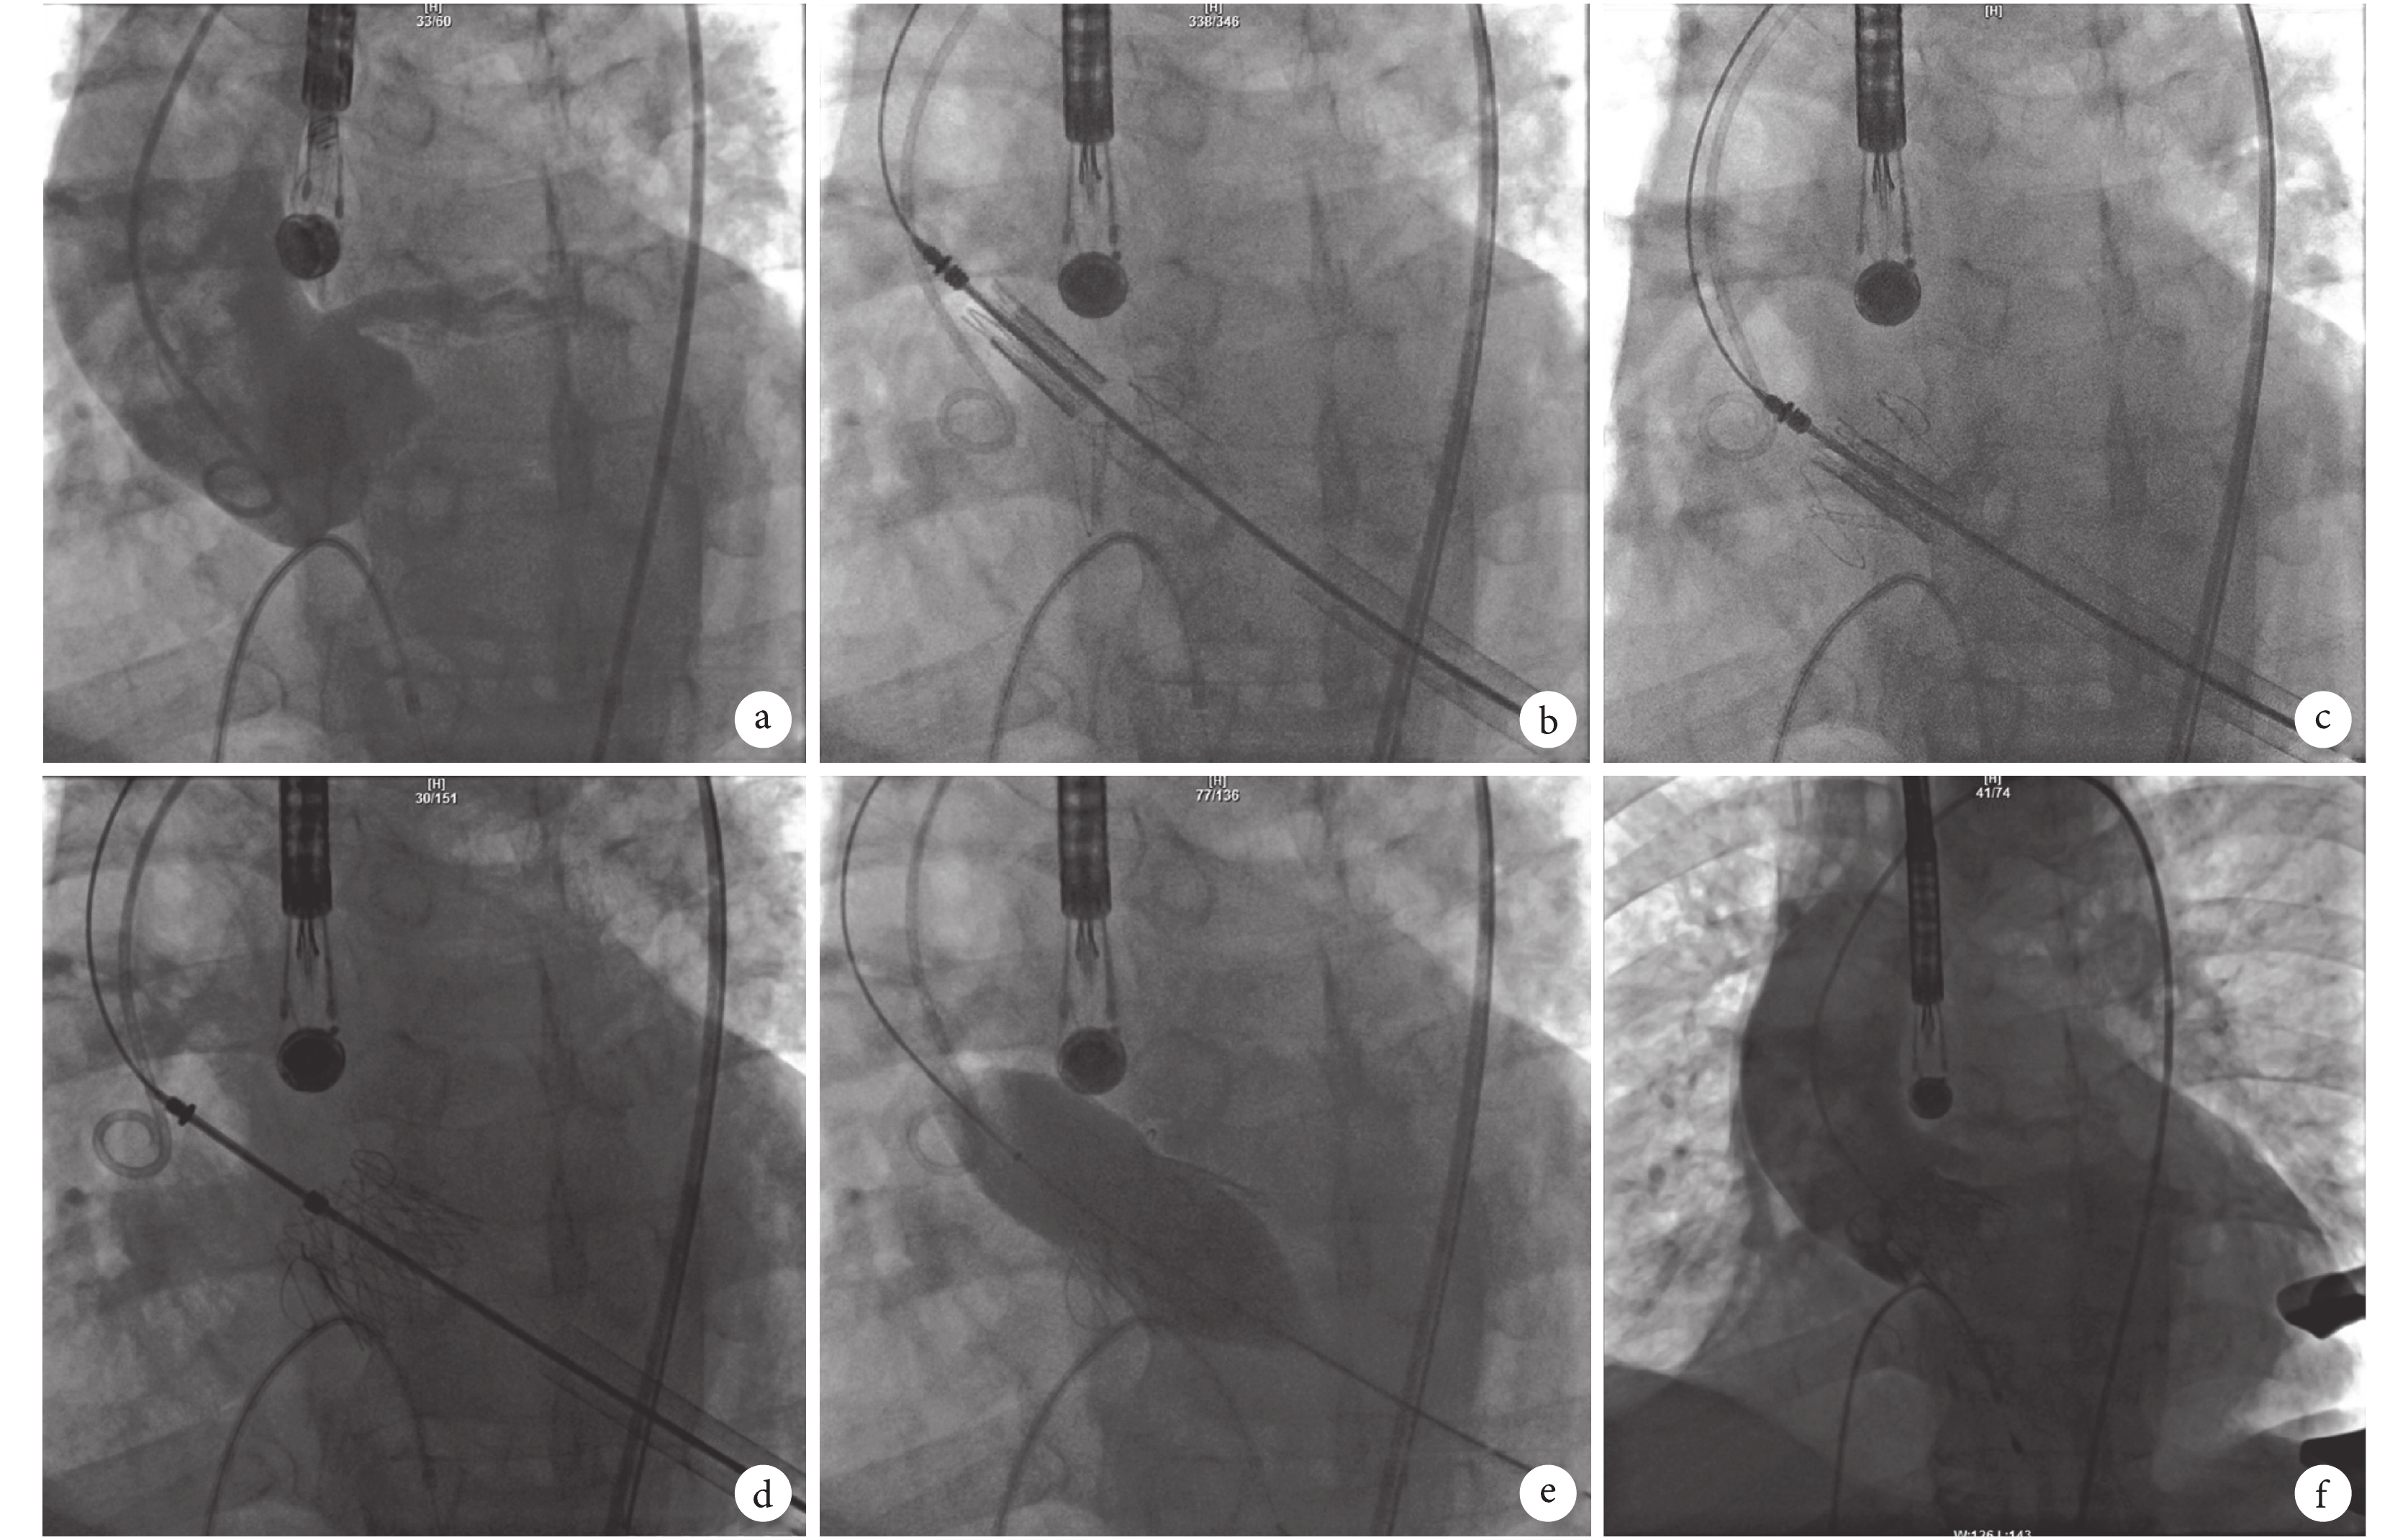

a:主動脈根部造影,確定最佳顯示角度;b:定位鍵釋放并錨定;c:TAVI 瓣膜下拉至定位鍵之間;d:人工瓣膜釋放,顯示呈梯形,提示釋放不完全;e:釋放后球囊擴張;f:球囊擴張后瓣膜釋放完全,功能正常,未見瓣周漏